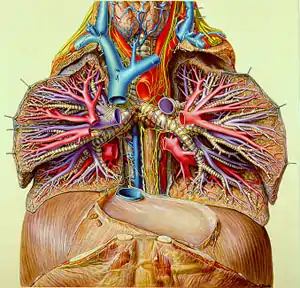

Eduard Pernkopf (November 24, 1888 – April 17, 1955) was an Austrian professor of anatomy who later served as rector of the University of Vienna, his alma mater. He is best known for his seven-volume anatomical atlas, Topographische Anatomie des Menschen (translated as Atlas of Topographical and Applied Human Anatomy; often colloquially known as the Pernkopf atlas or just Pernkopf), prepared by Pernkopf and four artists over a 20-year period.[1] While it is considered a scientific and artistic masterpiece,[2] with many of its color plates reprinted in other publications and textbooks, it has been in recent years found that Pernkopf and the artists working for him, all of them ardent Nazis, used executed political prisoners as their subjects.

Pernkopf instructed them to paint the organs they saw in as much detail as possible, to make them look like living tissue in print. This was enabled by a special treatment of the paper used for watercolor images that allowed greater detail than that type of paint normally did. The only deviation from this high level of realism was the use of color, where Pernkopf instructed them to use brighter hues than those found in real cadavers so that a reader would better learn to recognize and distinguish key anatomical landmarks.[2]

The first volume of the atlas was published in 1937. It was large enough that it required two books, one devoted to anatomy in general and the other covering more specifically the chest and pectoral limbs. Four years later, in 1941, the second volume, likewise requiring two books, came out. It covered the abdomen, pelvis and pelvic limbs.[2]

With the help of other parties, Dr. Israel directed a request to the University of Vienna to investigate the issue. This resulted in the establishment of the Senatorial Project of the University of Vienna "Studies in Anatomical Science in Vienna from 1938 to 1945" [13] in 1997. The project confirmed that at least 1,377 bodies of executed persons were delivered to the University during the Nazi times and its usage cannot be excluded from at least 800 images of the atlas. As a result, the atlas' publisher directed that an insert noting this possibility be mailed to all libraries holding the atlas, and stopped printing new copies.[14]

Scientists and bioethicists have debated whether it is acceptable to continue to use the atlas for instructional purposes in light of its possible provenance. Opponents have asserted that any use of the atlas makes the user complicit in Nazi crimes and that modern technology, such as the Visible Human Project (based on the tomographic dissection of a man executed in the United States), will make the atlas redundant if it has not done so already. Proponents have countered that the knowledge gained from the atlas can be ethically separated from its origins nor can it be in some cases easily replaced by modern technology or other atlases. "[Pernkopf's] atlas is still one of the very best in terms of accuracy, showing levels of detail concerning fascia and neurovascular structures that are of direct relevance for the actual dissection process," says Sabine Hildebrandt, a Michigan anatomy professor and German native who has researched him and other Nazi-era anatomists thoroughly.[16]